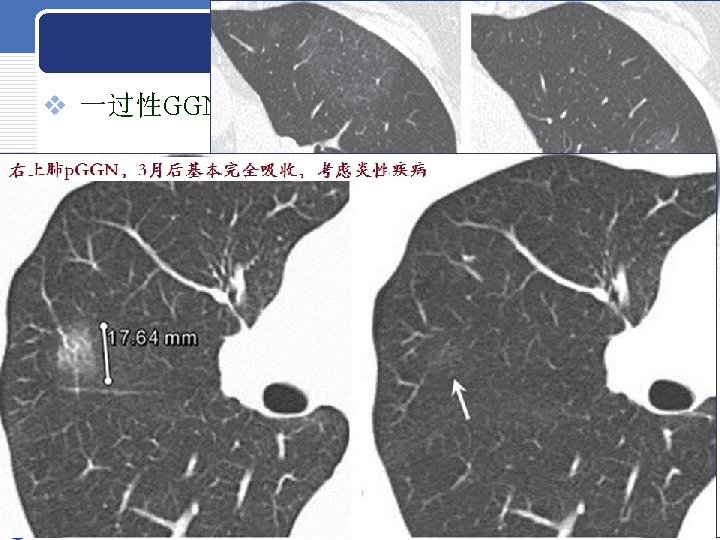

LUNG NODULE LUNG NODULE AAH p GGN 5